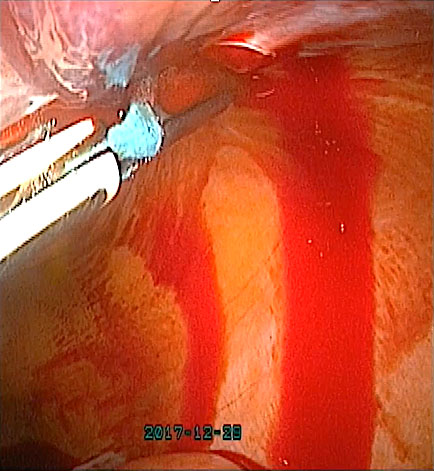

Vessel injury during dissection, especially with monopolar cautery/scissors (Figure 16A), can be managed if venous, by applying pressure with a gauze, and, if small, by holding it with an atraumatic dissector and the use of bipolar in bursts (Figure 16B).

(a) |

(b) |

16

(a) Scissor injury to left external iliac vein. (b) Bipolar cauterization in bursts.